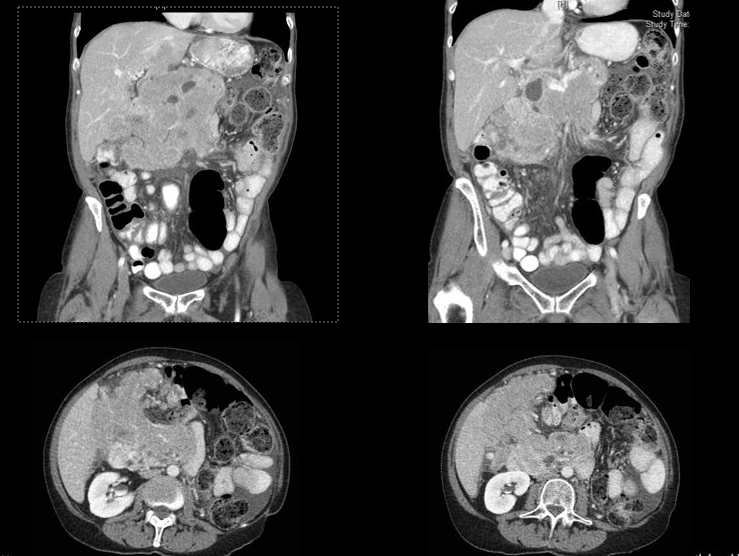

Imaging

CT scan shows:

• Large heterogeneous right upper quadrant mass

• No widespread bulky lymphadenopathy

What does this imaging pattern suggest?

a

Focal aggressive lesion

A large, heterogeneous, dominant mass without diffuse nodal disease supports a localized aggressive process, not typical CLL progression